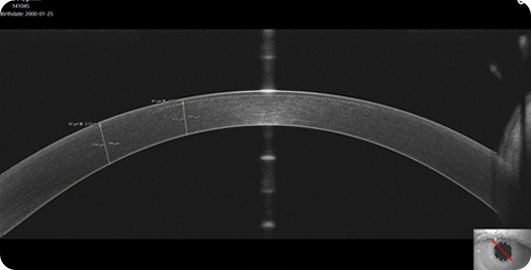

퍼펙트 올레이저수술을 완성하는 MS-39